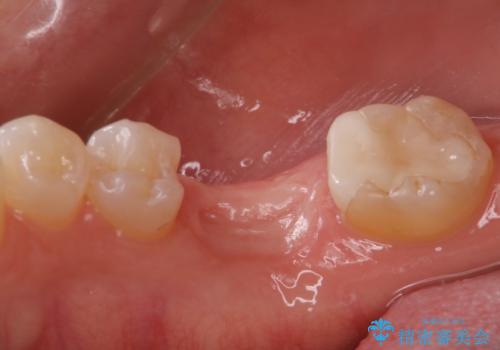

二回の手術を終えて最終的な被せ物が入るまで6〜8ヶ月かかると思います。

歯のなかったところをインプラント治療を行うことによってまた噛める喜びを感じていただけて良かったと思っております。